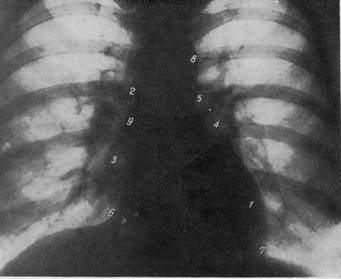

РЕНТГЕНОГРАММА НОРМАЛЬНОЙ ГРУДНОЙ КЛЕТКИ В ПЕРЕДНЕМ ПОЛОЖЕНИИ.

1 — дуга левого желудочка; 2 — дуга восходящей аорты; 3 — дуга правого предсердия; 4 — дуга ушка левого предсердия; 5 — дуга легочной артерии; 6 — правый кардио-диафрагмаль-ный угол; 7 — левый кардио-диафрагмальный угол; 8 — дуга аорты; 9 — правый атриовазалытый угол.